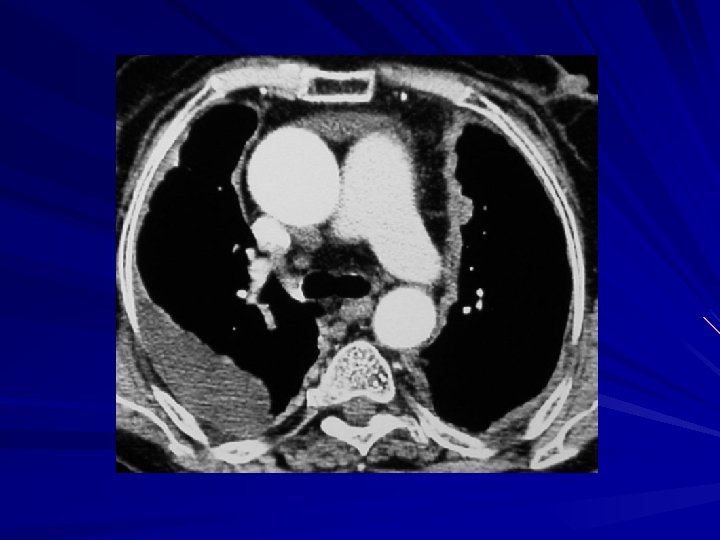

Plevral efüzyonda BT Çok duyarlı: minimal effüzyonlar saptanır Loküle effüzyonların saptanması Effüzyon – konsolidasyon ayrımı Ampiyem – apse ayrımı Nedeni ortaya koyabilir (pnömoni, malignansi, kalp yetmezliği, …) Benign – malign plevral hastalık ayrımı – %70 -80 doğruluk

Orta mediasten kitleleri Lenfadenopatiler – Lenfoma – Metastatik lenfadenopatiler – Sarkoidoz – Tüberküloz –… Mediastinal kistler (bronkojenik, özofagus duplikasyon) Anevrizmalar

Metastatik lenfadenopatiler